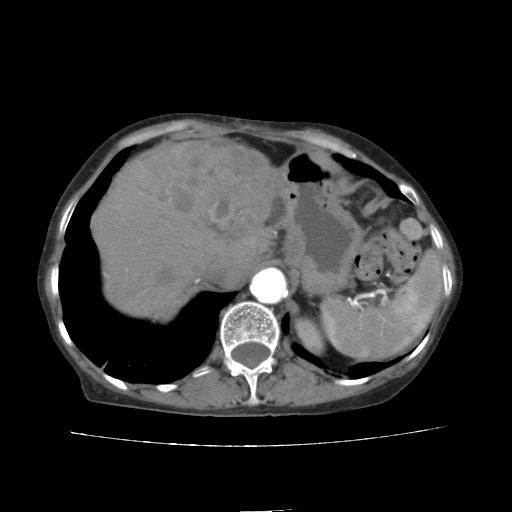

患者08年胆囊结石切除,之前没有做过ct,现在患者厌食。

平扫

看片子胆管里结石,肝上显示的占位会不会是胆管癌?大家帮忙看看,图像不太好,手头的处理文件没有,大致转换了一下,有原始图像数据